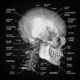

La anatomía de superficie se refiere al estudio de la configuración de la superficie del organismo humano y su relación con las partes más profundas del cuerpo. Esta disciplina se centra en la observación y descripción de las características externas y visibles del cuerpo, como los relieves óseos, los músculos, los vasos sanguíneos, los nervios y otros elementos anatómicos que se pueden palpar o visualizar en la superficie del cuerpo.

El objetivo principal de la anatomía de superficie es comprender las relaciones espaciales entre las estructuras superficiales y las estructuras más profundas del cuerpo humano. A través del estudio de la anatomía de superficie, se pueden identificar puntos de referencia anatómicos clave en la superficie del cuerpo que son útiles para localizar y describir estructuras internas. Estos puntos de referencia anatómicos se utilizan en la práctica clínica y la cirugía para determinar la ubicación de órganos, identificar áreas de interés y guiar procedimientos médicos.

La anatomía de superficie es particularmente útil en el diagnóstico y tratamiento de enfermedades y lesiones. Al examinar la superficie del cuerpo, los médicos y otros profesionales de la salud pueden identificar cambios o alteraciones en la configuración anatómica que pueden indicar la presencia de enfermedades o condiciones específicas. Por ejemplo, la observación de deformidades en la columna vertebral en la superficie del cuerpo puede sugerir la presencia de una escoliosis o una hernia discal en la columna vertebral.

Además de la observación visual, la anatomía de superficie también se basa en la palpación, que es la técnica de tocar y sentir las estructuras anatómicas a través de la piel. La palpación permite evaluar la consistencia, la textura, la temperatura y la sensibilidad de las estructuras superficiales, lo que proporciona información adicional sobre la salud y el estado de los tejidos y órganos subyacentes.